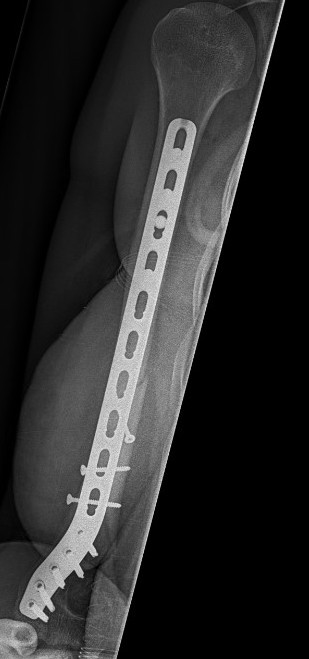

Humeral Fracture SegmentalHumeral Plate LateralHumeral Plate Long AP

Segmental fracture ORIF